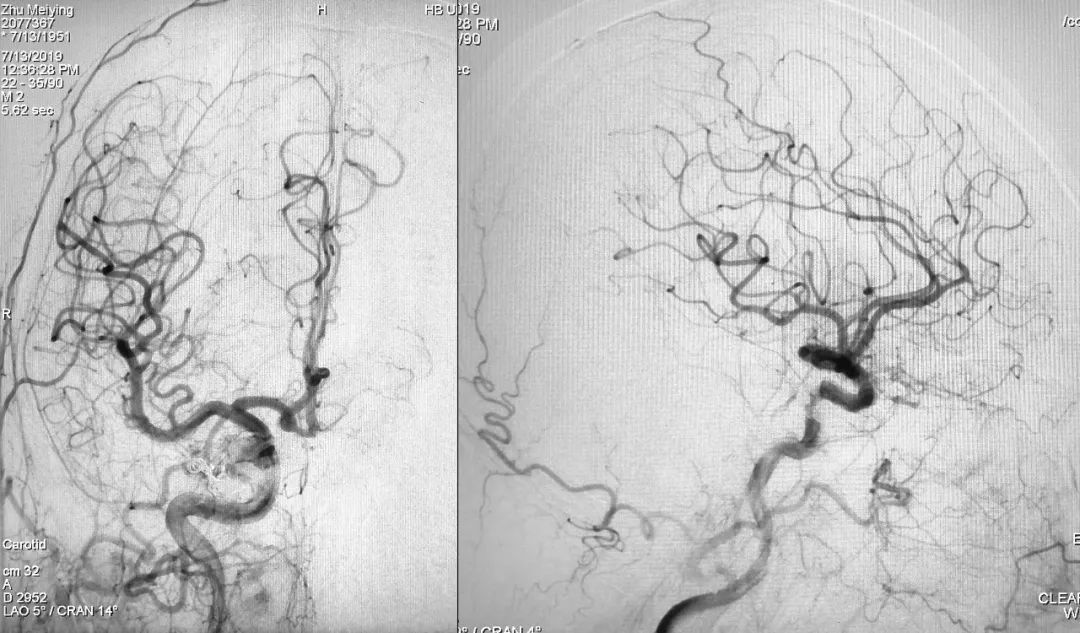

右侧颈内动脉正、侧位造影:

左侧颈总动脉正、侧位造影: